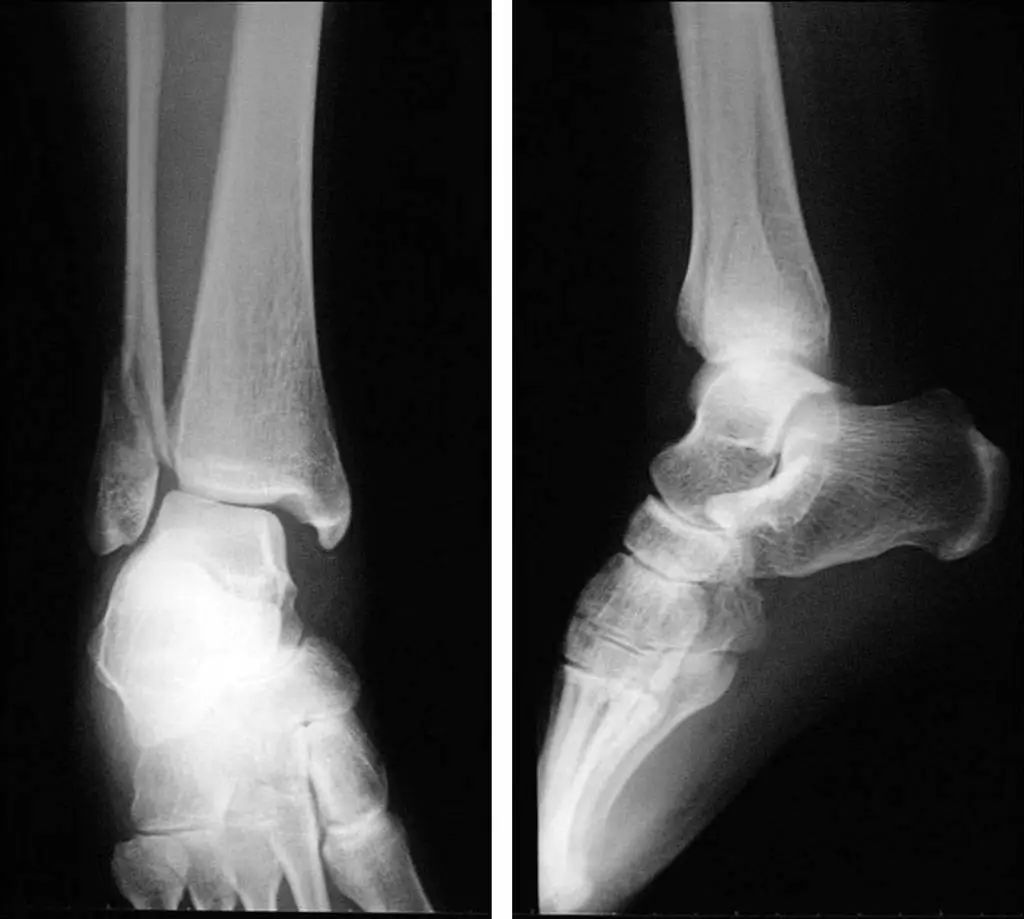

При серьезном повреждении голеностопного сустава внутренняя и внешняя лодыжки и таранная кость смещаются на 11 различных градусов (рис. 11).Статические рентгенограммы не точно отражают стабильность голеностопного сустава.Стресс-рентгенограммы и МРТ могут улучшить оценку стабильности голеностопного сустава и повреждения связок (рис. 12).

Рис. 11. Смещение перелома, по-видимому, в сочетании с вывихом.

Рисунок 12. Рентгенограмма под нагрузкой (разрыв треугольной связки)